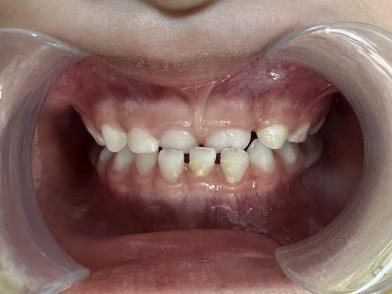

案例二:

治疗前